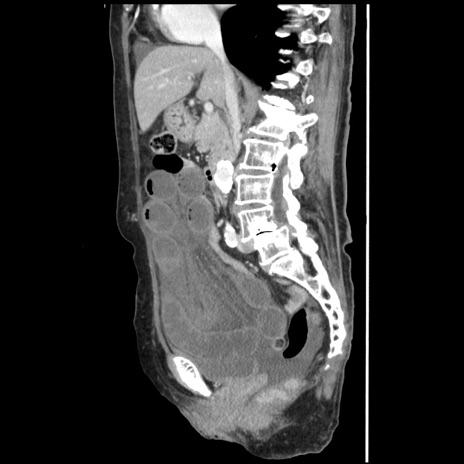

症例1(矢状断像)

【症例】80歳代女性

【主訴】腹痛

【現病歴】8時間前から腹痛あり来院。

【既往歴】糖尿病、脂質異常症、子宮体癌にて子宮全摘術

【身体所見】意識清明・会話良好だが腹痛で苦悶様、全腹部にわたって反跳痛と圧痛あり

【データ】WBC 13600、CRP 0.14、LDH 224、CK 90